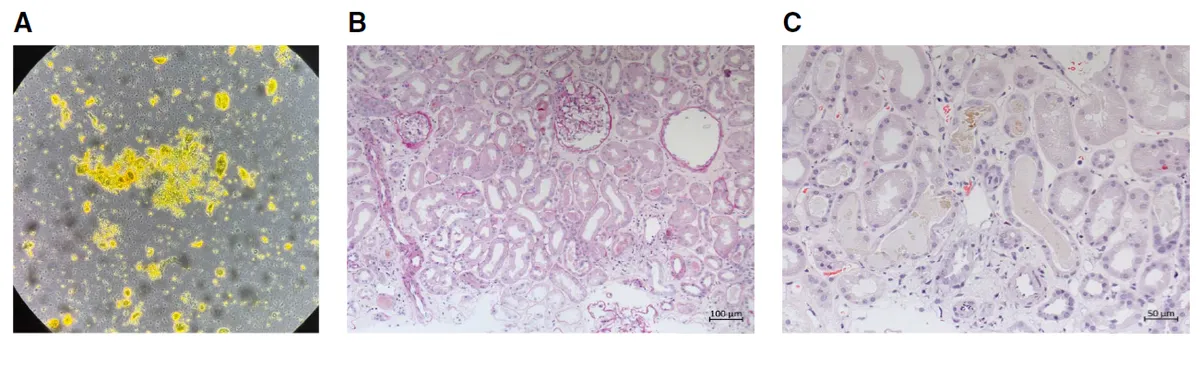

O sedimento urinário revelou cilindro biliares, cristais de leucina e células tubulares — achados que direcionam o raciocínio para lesão tubular por pigmentos.

Foi realizado biópsia confirmando existência de necrose tubular aguda com cilindros biliares, compatível com Nefropatia Colêmica.

**Figura 1.** Achados urinários e histológicos da biópsia renal. (A) O sedimento urinário mostra células epiteliais tubulares, cilindros granulares corados por bile e cristais de leucina. (B) Os túbulos renais apresentam células epiteliais achatadas e perda da borda em escova (NTA). (C) Os túbulos exibem cilindros amarelo-esverdeados corados por bile (H&E).

A biópsia mostrou:

• necrose tubular aguda difusa,

• cilindros biliares verde-amarelados ocupando túbulos,

…selando o diagnóstico de Nefropatia Colêmica.